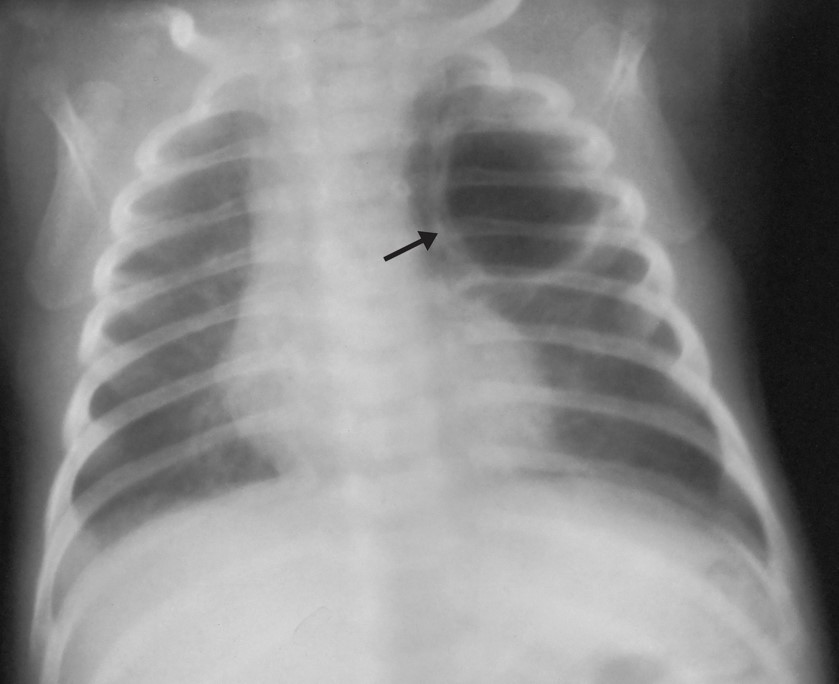

Intubação seletiva em recém-nascido